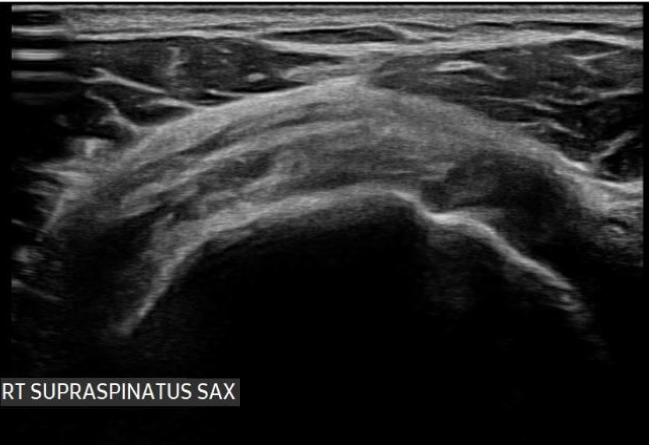

Each treatment begins with a thorough evaluation, including imaging and diagnostic tests, to identify the exact source of shoulder discomfort. Precision-guided injections deliver regenerative solutions directly to the affected area, promoting tissue repair, reducing inflammation, and supporting long-term shoulder stability for daily activities and athletic performance.

From diagnostic ultrasound to image-guided injections, every step of your shoulder care is performed with high-level precision and modern technology, ensuring accurate treatment delivery and better outcomes.